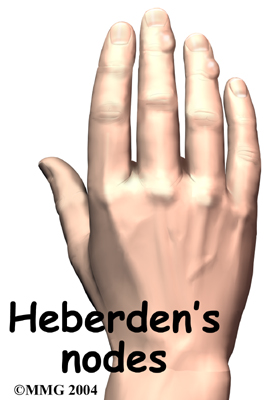

Osteoarthritis causes similar enlargements over the DIP joints, called .